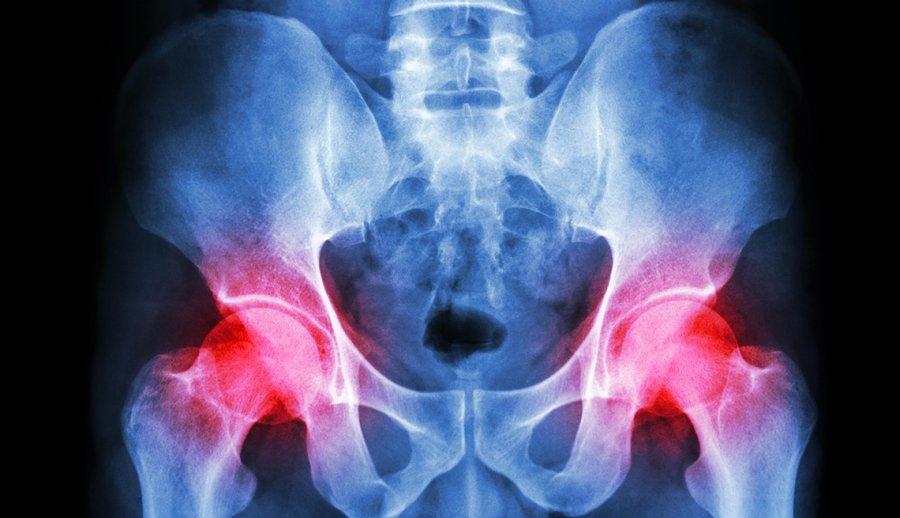

Climbing stairs after hip replacement surgery. 2 replies 46k views wesso forumite. Unless you meet the criteria below hip knee replacement is considered a pre existing medical conditionthis doesnt necessarily mean you cant get travel insurance but youll need to disclose your condition when youre booking your travel insurance.

This is why ervs medi care offers a thorough online screening process or the option to call our team and have someone help you through a telephone medical screening process. A travel insurer will need to understand your medical conditions and any replacement joints before providing you with a travel insurance policy. Running after hip replacement surgery.

If you have had any hip replacement surgery or resurfacing then you will need to have a travel insurance policy in place before you start your trip. Not recommended see above section. 15 may 2009 at 458pm edited 30 november 1 at 100am in overseas holidays travel planning.

We do insurance from 15 a week but always get people that have any medical condition or are on long term medication to call the medial screening line. Hip knee replacement and travel insurance. Hip replacement travel insurance covers you if you have had a hip replacement and wish to travel with confidence.